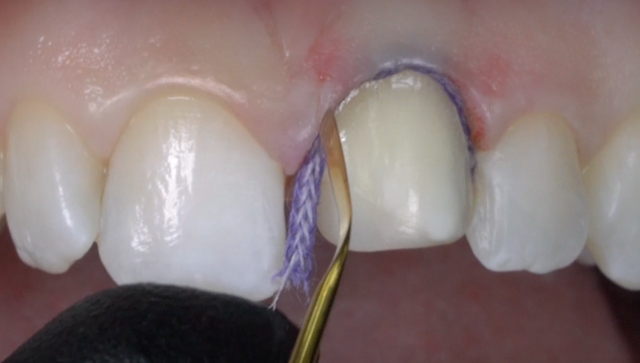

The first apically-located cord is generally a smaller diameter and will remain in place during the entire procedure. The purpose of the first cord is to retract the tissues in an apical direction and to block thin material remnants torn from the set impression from penetrating and remaining in the sulcus. It’s recommended to start rolling the first cord from the interproximal area where the sulcus depth is larger and the tissue (papilla versus free gingival margin) is stiffer, allowing the cord to be fixed more easily.

In most cases, the second superficial cord is impregnated with hemostatic/astringent solution and placed at the level of the finishing line so that its superficial part is always visible after insertion. This superficial cord is typically thicker than the first cord and aimed at laterally deflecting the gingiva and creating enough space for the impression material to capture the preparation margin.

The diameter of the second cord should be chosen according to the amount of deflection needed, considering the gingival biotype. Due to the difference in the positioning of the finishing line into the sulcus, two sizes for the second cords were chosen. Tooth #8 (11) being prepared for a full crown would need more deflection of the soft tissues to expose the preparation margin, so a #0 cord in size (Ultrapack, Ultradent Products, Inc., USA) was chosen. Tooth #9 (21) has been more minimally prepared for a veneer, so a thinner cord #00 would ensure the necessary deflection.